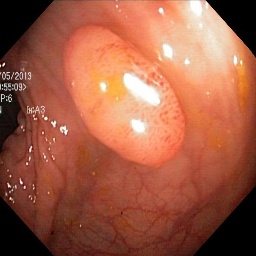

Refer to caption Refer to caption Refer to caption Refer to caption Refer to caption Refer to caption

(a) (b) (c) (d) (e) (f)

Figure 4: Visual comparison of segmentation performance with UNet architecture when synthetic data is used. (a) Input Image. (b) Ground Truth. (c) Baseline (UNet) only with 800 real data (d) real data +800 (e) real data + 1600 (f) real data + 2400.